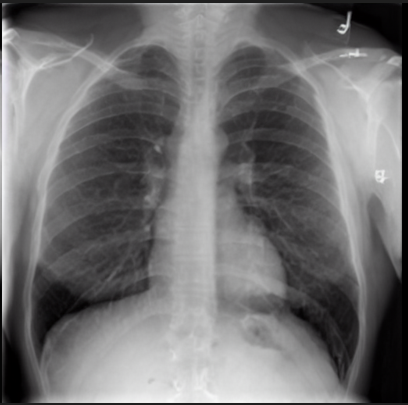

4.1 Qualitative Evaluation of Healthy Counterpart Generation

Example images from the disease COVID-19 Radiography Database and their generative healthy counterparts are given in figure 2. The images on the far left are instances of the lung opacity class from the real images in the dataset. The images in the middle column are examples of the generated healthy counterfactuals obtained via latent space diffusion, with RadBERT-guided textual-conditioning via a conditional prompt “normal chest x-ray”. A total of 75 diffusion inference steps are used with image conditioning strength=0.85 and guidance scale=7.5. (The former indicates the level of constraint on changes to the original input image and the latter is the weight given to the textual encoder conditioning in the generation of the image, ranging over [0,1] and [0,9], respectively).

Side-by-side inspection of the generated healthy counterfactuals (as per fig. 2) suggests that, as required, only minimal perturbation is made to the original image with respect to healthy pixels -i.e. localized image sites without structural medical defects. (In the top row, the medical structural defect in the original image is due to a lung opacity, and characterized via a relatively complex interaction between the imaging modality and subject manifesting as ‘gaps’ in the corresponding portions of the lung scan). The healthy/non-healthy discrepancy maps in all of these cases are obtained via masked subtraction of the original image from the generated image (the ground truth segmentation masks correspond to the broad area of interest –i.e. the complete lung). The generated healthy tissue is thus a subset of the mask and is shown in the final column of fig. 2 for the respective cases.

In the context of a VANT-GAN[20]-based approach, this highlighted material constitutes the diagnostic counterfactual visual attribution, i.e. the selection of material relevant to the diagnosis of the unhealthy condition. Healthy counterfactual generation was performed for the complete datasets in the three unhealthy classes, i.e Lung opacity, Viral Pneumonia and COVID, examples of which are given in fig. 3 for the three classes (all of the generated healthy counterfactuals from this experiment can be found on https://huggingface.co/ammaradeel/diffusionVA). Visual inspection indicates that the generated counterfactuals are, in general, visually plausible with minimal perturbation made to the unhealthy image overall. Moreover, the healthy counterpart generation does not appear to unnecessarily affect aspects of the images unrelated to the medical condition, the model selectively making changes to the unhealthy regions in a structurally plausible manner, e.g. generating missing portions of the lung without generating extraneous lung material where it would be expected to normally exist (e.g. in the abdominal cavity).